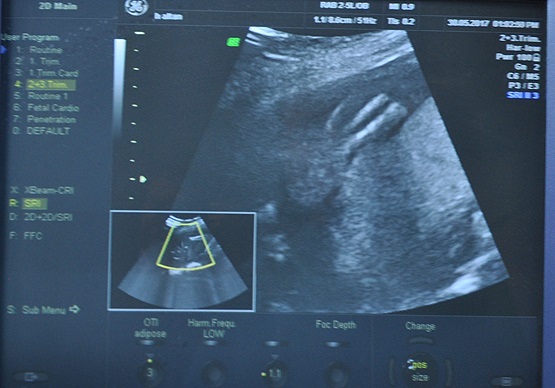

Konya Necmettin Erbakan Üniversitesi Meram Tıp Fakültesi Hastanesine başvuran 5 aylık hamile Hanife Altan'ın (20) kız bebeğine "Amniyotik band sendromu" teşhisi konuldu.

İçinde bulunduğu amniyon sıvısıyla dolu zarın parçasının ayrılarak, sol ayağını sarıp sıktığı görülen bebeğin ayağının tamamen kaybolma ihtimali olduğu tespit edildi.

Meram Tıp Fakültesi Kadın Hastalıkları ve Doğum Ana Bilim Dalı Öğretim Üyesi Prof. Dr. Ali Acar, kan akışı sağlanamadığı ve ayakta gelişim geriliği olduğu için bebeğe anne karnında müdahale etti.

Henüz 300 gramlık bebeğin ayaksız doğmaması için Acar ve ekibi riskli operasyonu başarıyla gerçekleştirdi. Sağlık durumu iyi olan ve doğuma kadar düzenli takip edilecek bebeğin ayaksız doğmasının önüne geçildiği bildirildi.

Prof. Dr. Ali Acar, tetkiklerde zarın parçasının sardığı ayakta kan akışının durduğunu hatta ayak parmağın birinin de iyice küçüldüğünü gördüklerini söyledi.